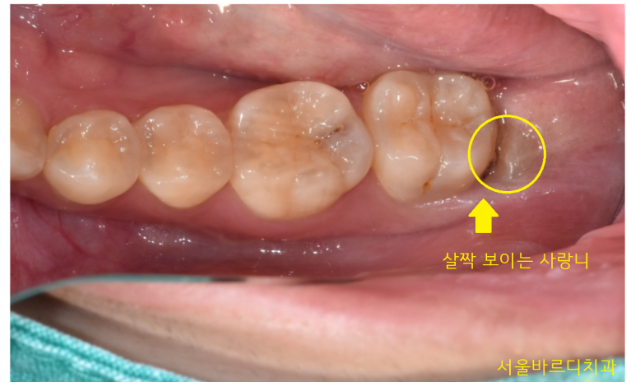

환자분은 사랑니가 살짝 보이는

머리 일부만 올라와있는 상황이었습니다.

그러다보니 잇몸 틈새 사이로 음식물이 자꾸 끼고

붓고 아프시다고 하셨어요.

강동구 사랑니 발치를 원하셨습니다.